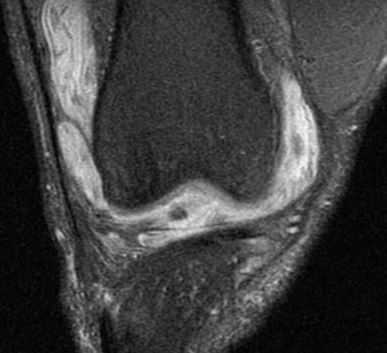

При МРТ коленного сустава наблюдается выпот по типу синовита, утолщение синовиальной оболочки и наслоения на ней.

МРТ коленного сустава. Т2-взвешенная корональная МРТ с подавлением сигнала от жира. Болезнь Лайма.